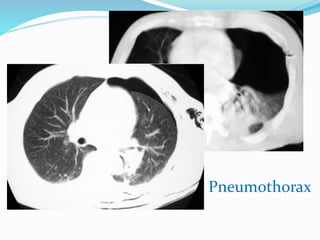

PNEUMOTHORAX

2e question : pneumothorax ?

 Un petit pneumothorax : peut être difficile à voir.

 Radioghraphie thoracique debout : visibilité la

plèvre viscérale, région de l`apex pulmonaire, pas de

vaisseaux entre cette ligne et la paroi thoracique.

 Radiographie thoracique couchée : l`air

intrapleural a des localisations différentes. La partie la

plus haute située au niveau de la base pulmonaire

(chercher l`hyperclarté de la base droite, cul de sac

costo-diaphragmatique latéral, une coupole

diaphragmatique trop bien visualisée).

Syndrome pleural

localisé du

sommet droit

apical et latéral

droit

compressif

Réviation du médiastin

Refoulement du

diaphragme

Pneumothorax gauche en position couchée